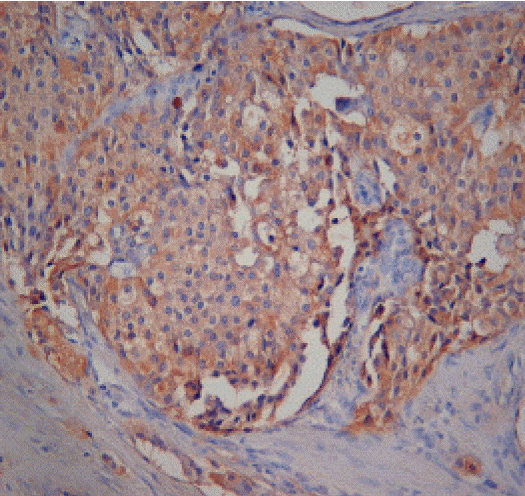

이후 수술을 시행하였고, 담낭 바로 아래 총담관 옆으로 약 1.5 cm의 종괴 관찰되어 종괴 절제 및 담낭 절제를 시행하였고, 수술 중 초음파검사에서 췌장 미부에 0.6 cm의 병변이 관찰되어 췌장 미부 절제를 시행하였다. 종괴의 동결조직 검사에서 악성 유무 확실히 알기 어려웠으며 이후 절제조직의 면역조직화학적 검사에서 가스트린에 양성을 보였고(그림 5), 시냅토피신, 크로모그라닌에 국소 양성 반응을 보이는 고분화 내분비성 종양이 두 병변 모두에서 관찰되어 추가적인 담도절제 및 임파선 곽청술을 시행하였고, 1개의 국소 림프절 전이 소견이 보여 악성 가스트린종에 합당한 소견이었다. 부갑상선 병변에 대해 부갑상선절제술 시행하였으며, 병리검사에서 부갑상선종 소견을 보였다. 수술 1주일 후 시행한 공복 혈중 가스트린 수치는 51 pg/mL으로 정상화되었다. 이후 고용량의 PPI (란소프라졸 하루 60 mg)로 지속적인 치료하였으나 식도 협착 악화되어 풍선확장술 2차례 시행하였다.

Figure 5.

Histologic findings of the resected specimen. The tumor cells show brownish discoloration in immunohistochemical staining for gastrin (×400).